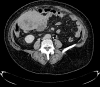

Presentation of case: We report a case of a 70-year's old female who presented with nausea and abdominal discomfort for 6 months. Workup revealed an abdominal mass. Patient was treated with surgical removal in a general hospital.